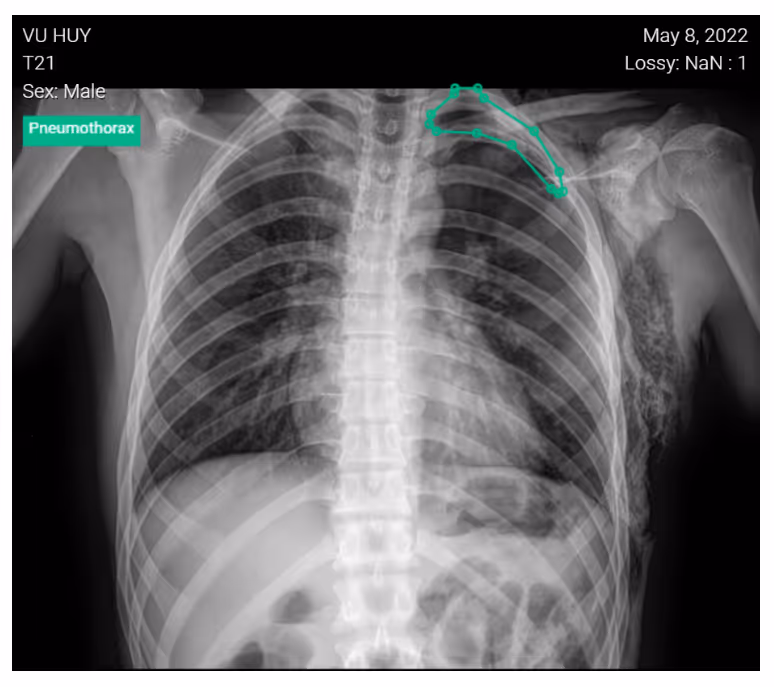

- A 20-year-old male presented with a stab wound to the left hemithorax, and crepitus of the chest was detected upon physical examination.

- Image findings:

- Chest radiograph revealed a left pneumothorax, marked by the visible left pleural edge

- No shift of the mediastinum

- Extensive subcutaneous emphysema over the left chest wall

DrAid for Pneumothorax helps to compare side-by-side images for follow-up in pneumothorax patients. This aided reading allows doctors to create a suitable treatment plan for the patient.Interested in deploying DrAid at your health facility?